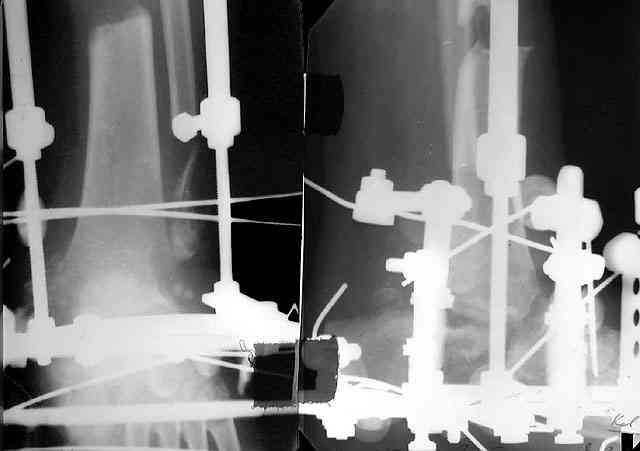

Не адресована другая проблемы - берцово-пяточный блок достигается ценой укорочения конечности на 3-4 см. Поэтому надо предусмотреть что-то для удлинения. У нас в клинике традиционный подход - билокально удлинять большеберцовую кость. Раньше еще и малоберцовую рубили на двух уровнях. Сейчас (спасибо коллегам из форума) пользуемся только

той остеотомией, которая делается для отворачивания кожно-костного лоскута с малоберцовой костью. Фиксируем все это аппаратом (пример в приложении) около 4 мес.

То есть относительно недолго. Про винты поэтому стоит вспомнить, только если опору со стопы хочется снять совсем уж рано. Можно, в принципе, и о штифтовании подумать. Правда, мы пока думаем - они так срастись успевают.

В итоге: мы планируем выполнить пациенту большеберцово-пяточный артродез в аппарате Илизарова с одновременной остеотомией берцовых костей и их последующим удлинением. Возможно, мы дополним фиксацию артродезируемых костей винтами.